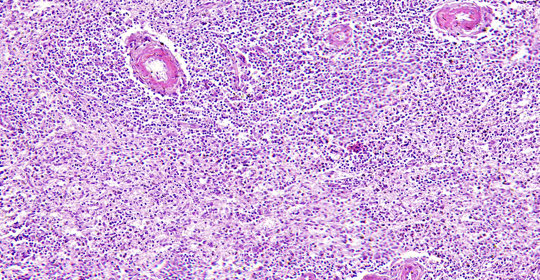

中樞神經系統感染:症狀、後遺症與診療

中樞神經系統感染:型別、傳染與治療

中樞神經系統感染:治療與預後